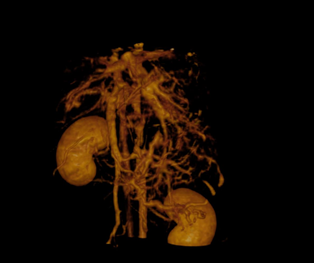

• Vaisseau